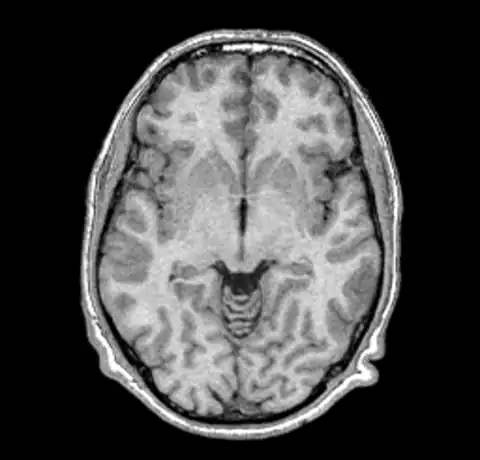

B0 non-uniformity is difficult to detect when simply looking at images without the assistance of a judiciously ranged color map. In our test case we'll start with a simple T1 MPRAGE image from a 1.5T Siemens scanner.

The above image and all the images here were created using mincpik in a similar fashion to the below.

mincpik -scale 2 original.mnc -slice 150 -image_range 10 80 original.png

Note that it is difficult to pick the non-uniformity in the image unless you look carefully at the intensity of the white matter in the lower parts of the image. In order to correct this image we run nu_correct with the default parameters.